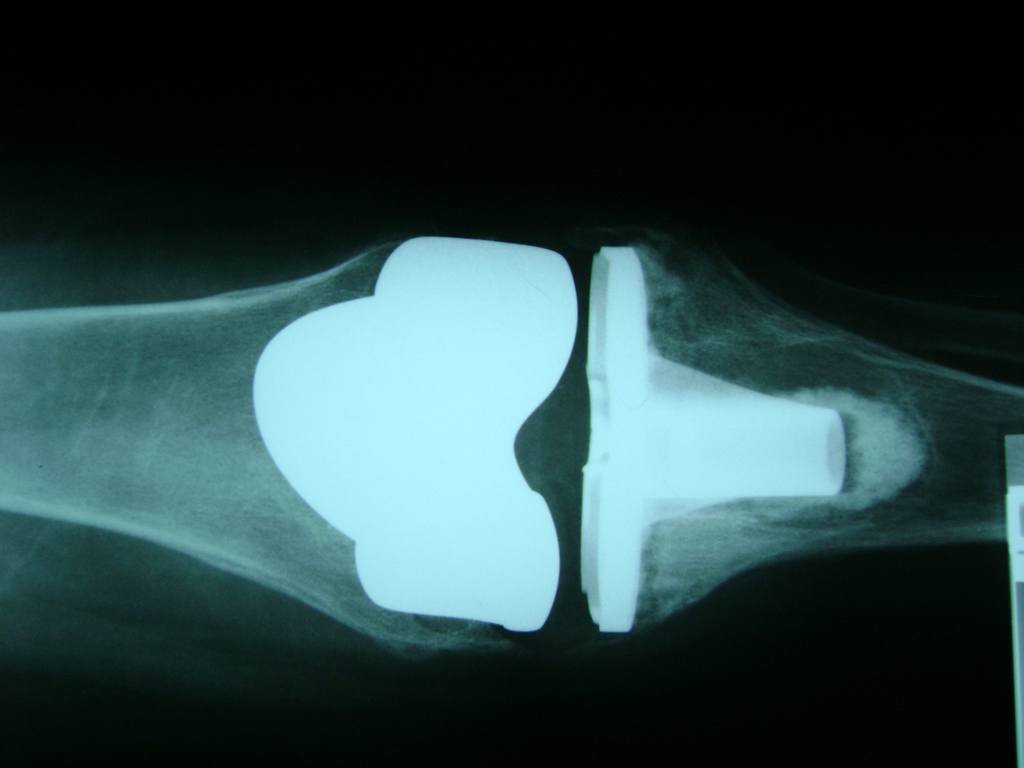

Húmero - Rodilla